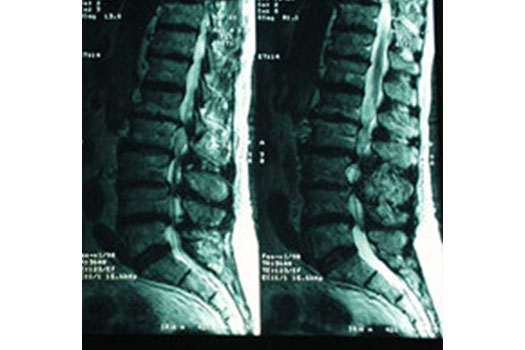

Pathologie dégénérative lombaire, Sciatiques et Cruralgies

Hernie Discale lombaire

Sténose lombaire

Spondylolisthesis lombaire

Discopathies